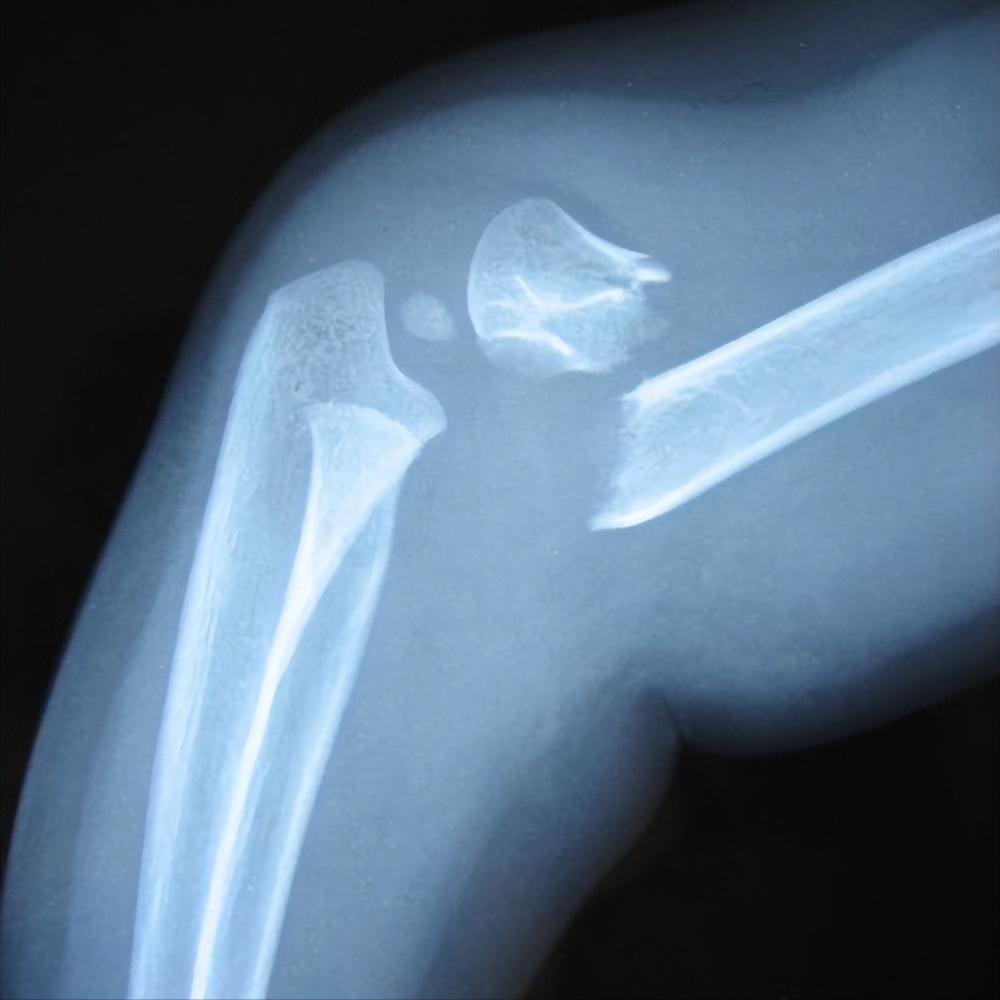

半月板损伤

修复半月板是一种纤维软骨组织,起减震器的作用,具有稳定和润滑关节、本体感觉和负荷分配等功能。 负重或外伤时突然的扭转运动可能会导致半月板损伤,从而导致疼痛、肿胀和活动困难等症状。

由于其缺乏血管组织,传统的药理学和外科治疗不能导致健康组织的再生。 采用压痛点注射PRP的方法慢性半月板损伤,发现治疗后1月、2月、3月的膝关节Lysholm评分分别均有明显改善,治疗后3月VAS明显下降。

且膝关节McMurray试验及半月板损伤程度较治疗前改善,以上发现说明PRP注射治疗慢性半月板损伤可缓解疼痛、改善体征,并促进半月板愈合 。也有其他研究也支持PRP治疗半月板损伤可有较好的临床疗效。

Kaminski等对比关节镜下修复半月板撕裂后修复部位注射PRP及生理盐水的疗效,结果表明PRP在半月板修复中促进了半月板愈合并改善了关节功能。

此外, 还有大量研究也表明关节镜下半月板修复联合PRP治疗半月板损伤可有效缓解患者症状、改善关节功能、促进半月板修复并改善预后 。而Yang等的研究认为PRP对半月板损伤术后患者的功能情况和半月板愈合率并没有明显改善。